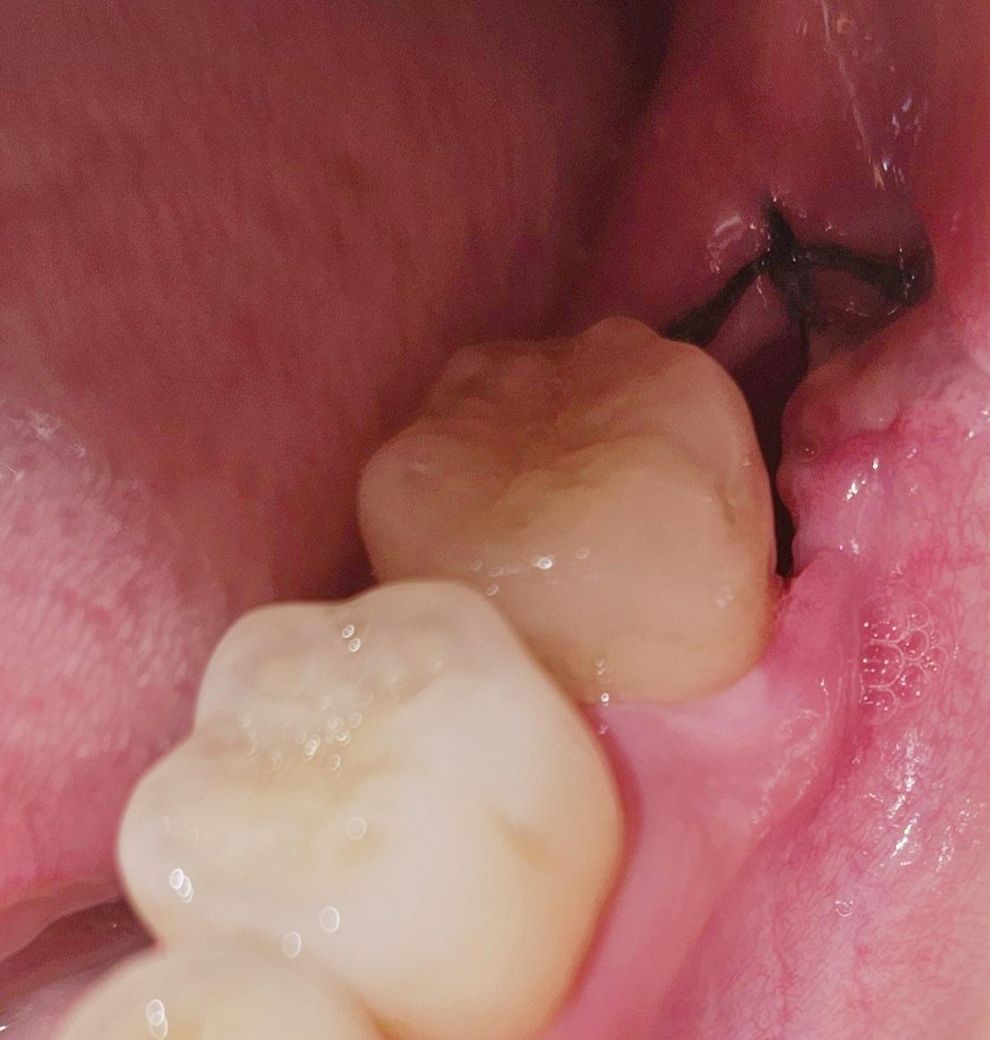

발치한지 5일 차인 오늘 촬영한

해당 부위의 사진들을 보시고

드라이소켓(건성발치와)인지 한번 봐주신다면

감사하겠습니다.

• 3번 째 사진

사진상에서는 드라이소켓으로 보이진 않지만 냄새가 심하거나 통증이 심하면 의심해볼 수 있습니다.

현재 사진상으로 드라이 소캣으로 보이지는 않습니다. 우선 진통제를 복용하면서 상태를 지켜보고, 만약 붓기 및 냄새 ,통증이 심해지는 경우에는 다시 치과진료를 받길 권합니다.